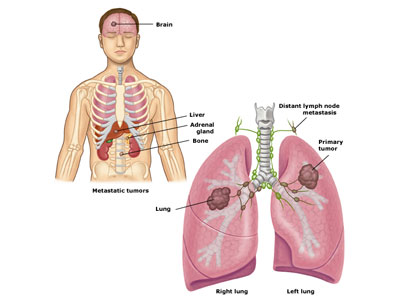

- 非细胞肺癌复发 图片合集

- 肺腺癌晚期转移到脑部还有救吗

- 非小细胞肺癌的免疫治疗